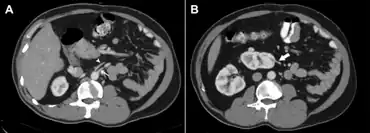

a) Origin of the left renal artery from the aorta b) left renal artery entering the lower pole of the ectopic kidney